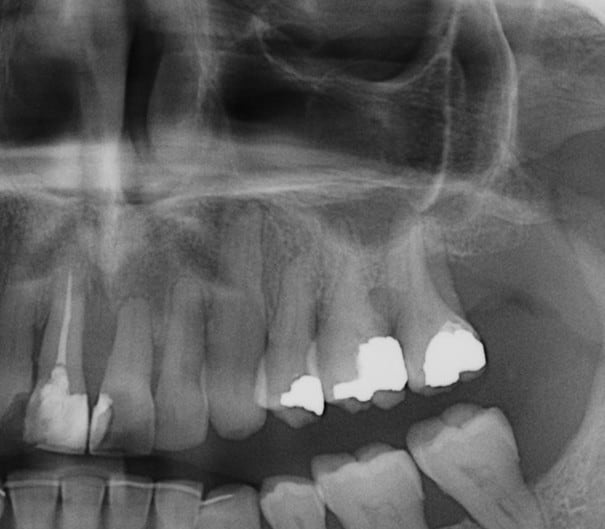

Plusieurs points: les vis de 15mm x 2mm qui transfixent c'est pas top, une seule plaque, qui plus est non réglable de chaque côté, c'est encore moins top. C'est une plaque de fracture.

En mandibulaire gauche c'est quoi ce fil d'osteosynthese? Un troisième fragment? En laissant l'apex de la 48 pile sur le trait d'osteotomie, je dis chapeau.

Pour la lésion de 42, ca peut être lié à la genio. Forage hasardeux? Mais je vote plus pour une lésion endo/paro

il y a de l'os autour de 11 et 21 ?

On dirait une chirurgie des années 90 :-(

Je ne suis pas fan des extractions multiple mais là, à part les secteurs molaires, je ne suis pas sur de pouvoir sauver quelques chose(surtout mandibulaire)